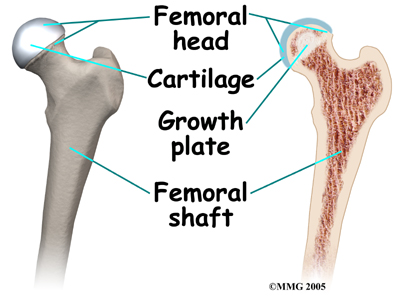

The hip joint is where the thighbone (femur) connects to the pelvis. The joint is made up of two parts. The upper end of the femur is shaped like a ball. It is called the femoral head. The femoral head fits into a socket in the pelvis called the acetabulum. This ball and socket joint is what allows us to move our leg in many directions in relation to our body.

In the growing child, there are special structures at the end of most bones called growth plates. The growth plate is sandwiched between two special areas of the bone called the epiphysis and the metaphysis. The growth plate is made of a special type of cartilage that builds bone on top of the end of the metaphysis and lengthens the bone as we grow. In the hip joint, the femoral head is one of the epiphyses of the femur.

The capital femoral epiphysis is somewhat unique. It is one of the few epiphyses in the body that is inside the joint capsule. (The joint capsule is the tissue that surrounds the joint.) The blood vessels that go to the epiphysis run along the side of the femoral neck and are in danger of being torn or pinched off if something happens to the growth plate. This can result in a loss of the blood supply to the epiphysis.